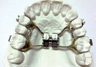

Principali tipi di apparecchio

L’apparecchio mobile (si può mettere e togliere da soli) è di solito usato nella prima fase di trattamenti di bambini, per espandere il palato o guidare la masticazione in posizione corretta e, ancora, per correggere abitudini come succhiare il dito e respirare con la bocca.

Gli apparecchi fissi (possono essere messi e tolti solo in studio) sono solitamente usati negli adolescenti quando quasi tutti i denti permanenti sono presenti. Consistono di attacchi (detti anche brackets) incollati sui denti: ogni attacco è unito agli altri da un filo metallico che può essere modellato o sostituito durante le visite di controllo.

ESPANSORE PALATALE

Allarga un palato troppo stretto in modo da creare spazio in caso di denti troppo affollati.